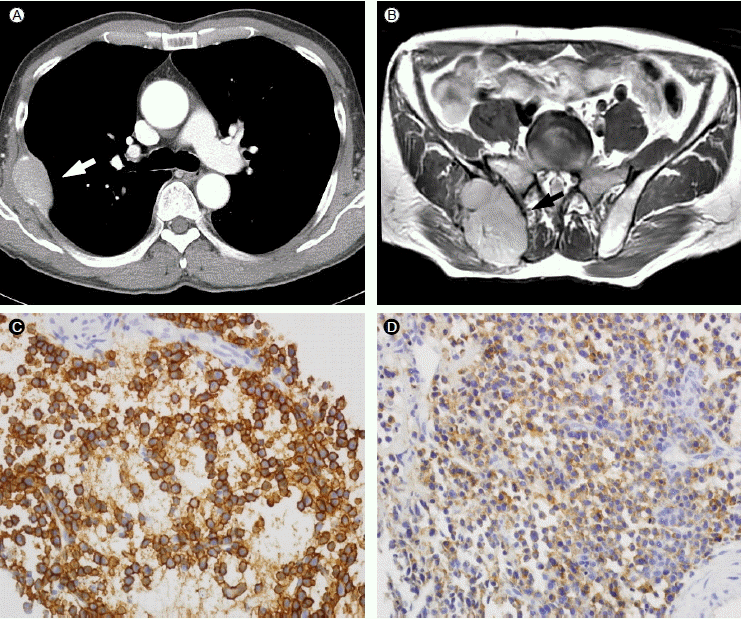

Figure 3.

Computed tomography shows multiple soft tissue masses in the stomach (A), pancreas (B), pelvic cavity (C), and right buttock (D) (arrows).

(A) Gastroscopic examination revealed two polypoid masses with irregular surfaces covered by blood clots and whitish plaques in the body and anterior wall of the stomach. A biopsy of the mass showed the diffuse infiltration of plasma cells (B, H & E stain, ××400) that are positive for CD 138 (C) and lambda light chain (D) on immunohistochemical staining (×400).

병리소견: 위내시경을 이용한 위 덩이의 조직검사에서 CD138과 lambda 경쇄에 대한 면역조직화학 염색에 양성인 형질세포종으로 확인되었다(Fig. 4).

Figure 4.